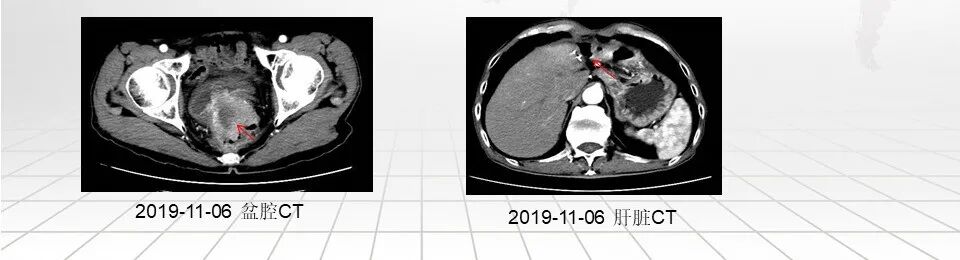

2019年11月患者出现肛门坠胀伴疼痛,伴有小便带血,就诊我院。

行腹盆腔CT检查提示:直肠癌术后,吻合口周围软组织密度影,考虑复发,累积膀胱后壁。肝左叶术后改变,残肝实质密度未见明显异常。

电子肠镜:插入肛缘即可见溃疡浸润型病灶,表面溃烂明显,边缘不规则隆起,质脆易出血,肠腔狭窄,无法进镜,考虑直肠癌术后复发可能。 -

病理诊断结果:腺癌

经医院第二次MDT会诊后,结合患者病史及辅助检查,明确诊断直肠恶性肿瘤术后,肝转移术后,残端局部复发。考虑患者高龄,既往有两次大手术史,局部晚期,不宜手术治疗,建议内科治疗。